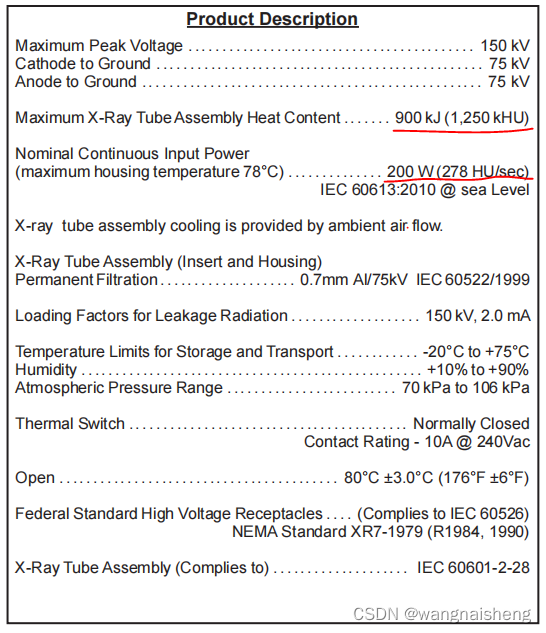

VARIAN_RAD_14球管参数如下:

该球管容许的最大热容量为1250kHU,单次曝光容许的热容量为278HU/sec。